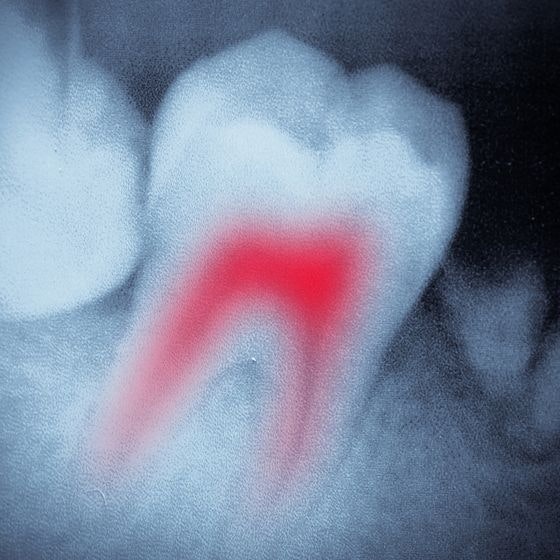

While porcelain can't decay, the tooth beneath your crown can. You must still abide by an oral care routine that involves brushing, flossing, and using mouthwash.